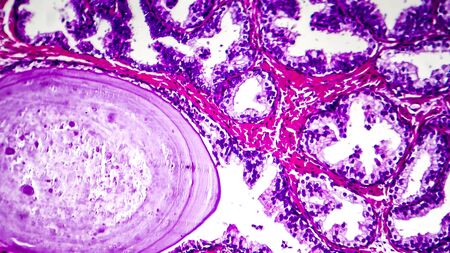

Light micrograph of teratoma, a tumor made up of several different types of tissue, such as hair, teeth, muscle, or bone. Teratoma is typically found in the ovary, testicle, or coccyx